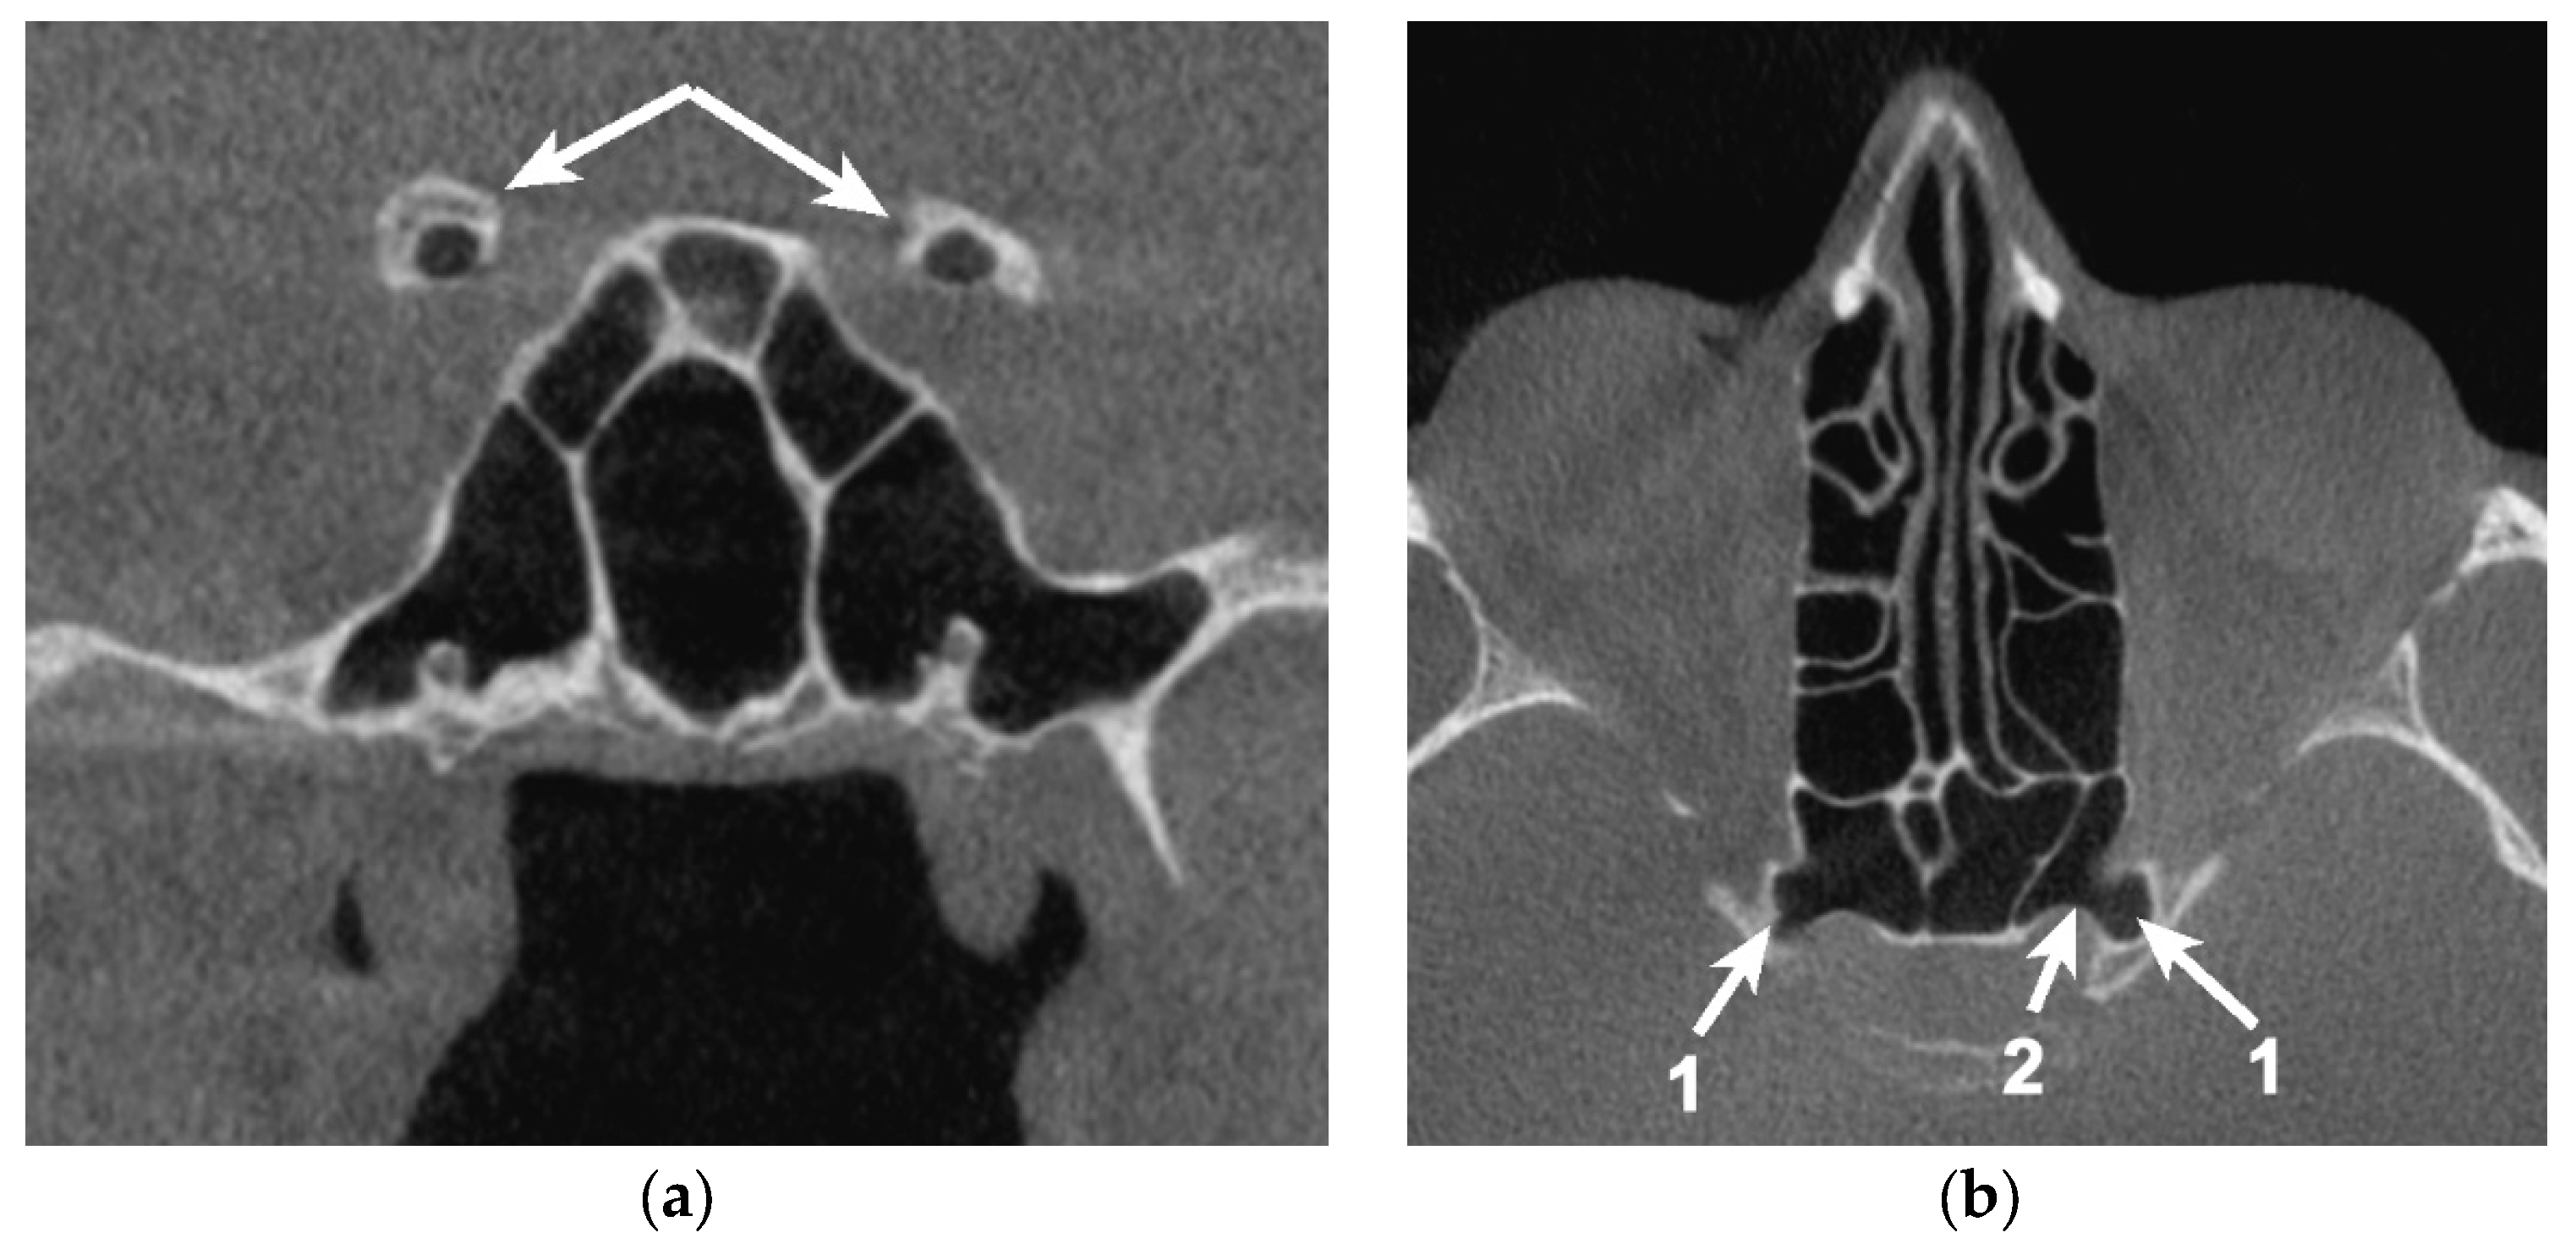

Figure 4. Bilateral sagittal CBCT reconstruction, demonstrating the pattern of pneumatization of both the optic strut and anterior root (AR) of the lesser sphenoidal wing. (a) Left side. (b) Right side: 1. Pneumatized AR; 2. Pneumatized OS; 3. Onodi cell; 4. Sphenoid sinus.